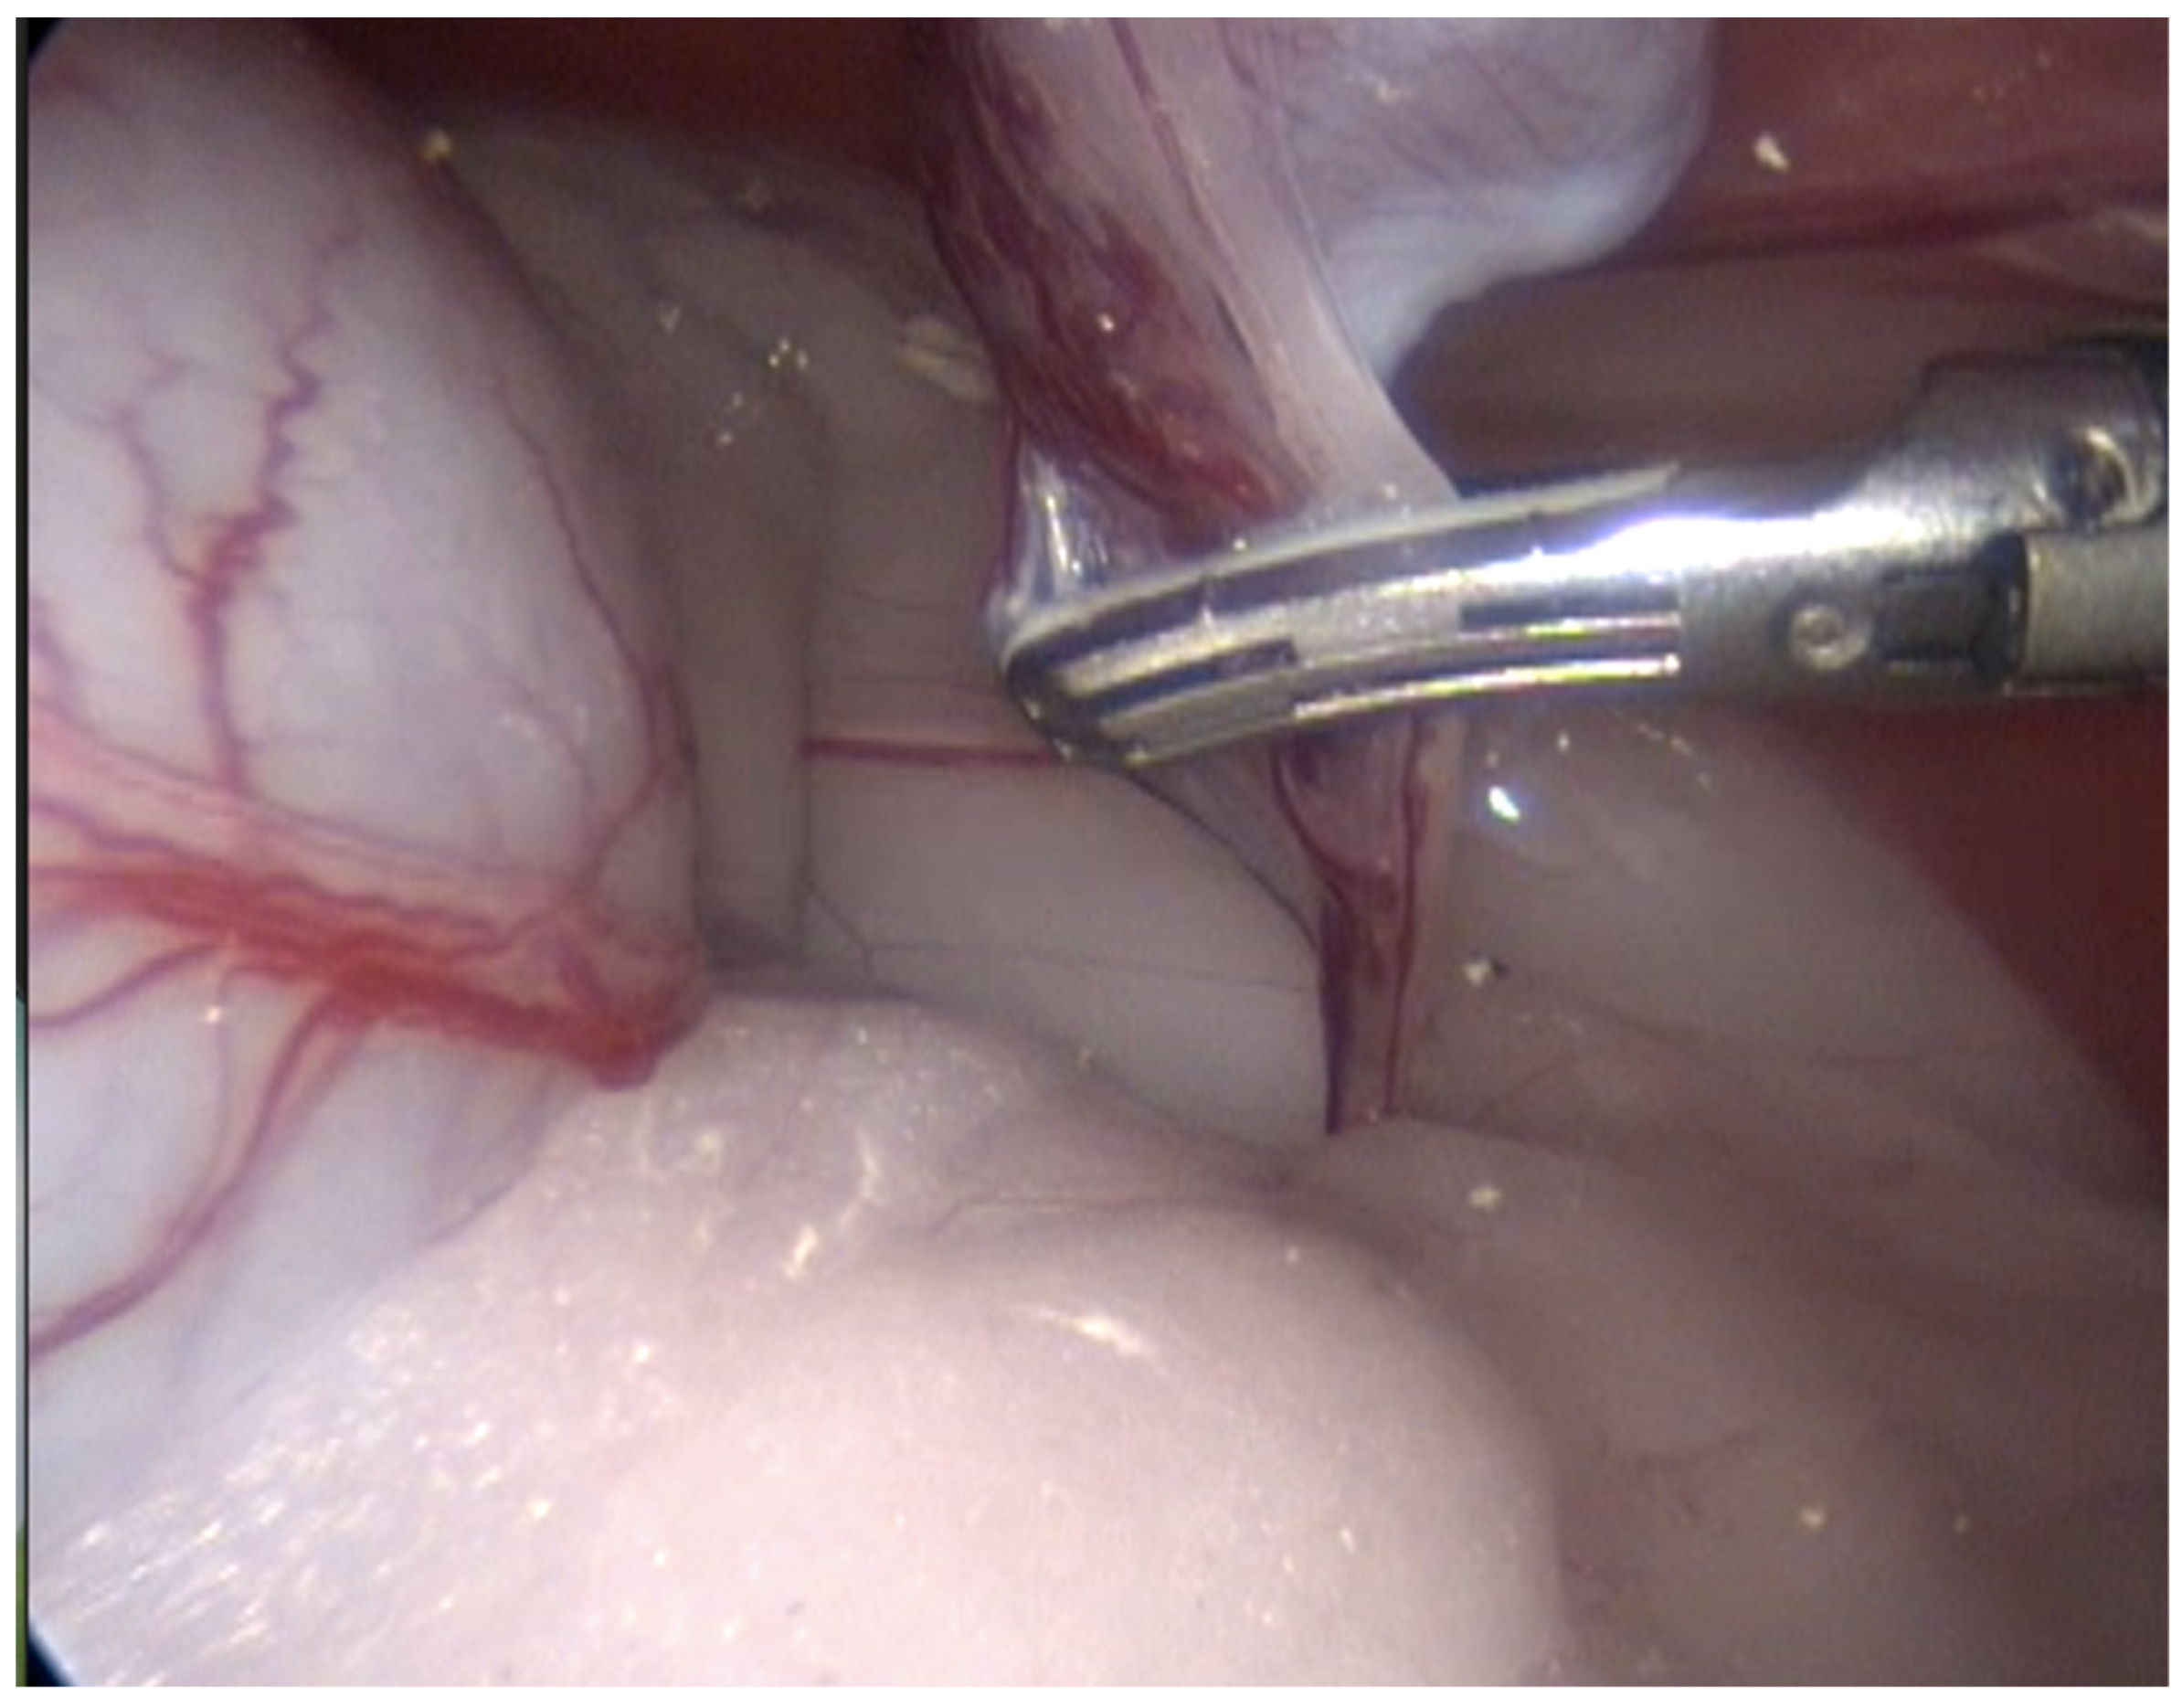

In 13 cases, the coagulation and cutting of the vascular pedicle, the spermatic cord, and the gubernaculum were performed with advanced electrothermal bipolar energy devices (eight with the Laparoscopic Tissue Sealer G2-ENSEAL® Ethicon-Johnson & Johnson (New York, NY, USA) and five with LigaSureTM Covidien-Medtronic (Dublin, Ireland), https://www.jnjmedtech.com/global, https://www.medtronic.com/covidien/en-us/index.html accessed on 27 October 2022) (Figure 3). In five cases, this procedure was made with a Harmonic scalpel device (Figure 4 and Supplementary Video S1) (Harmonic ACE® +Shears and Gen11 generator Ethicon-Johnson & Johnson), and in one case, with the use of a monopolar energy hook.

Figure 3.

Technique with two access ports. View of the coagulation and cutting maneuvers of the vascular pedicle, spermatic cord, and gubernaculum, performed with an advanced bipolar energy device.